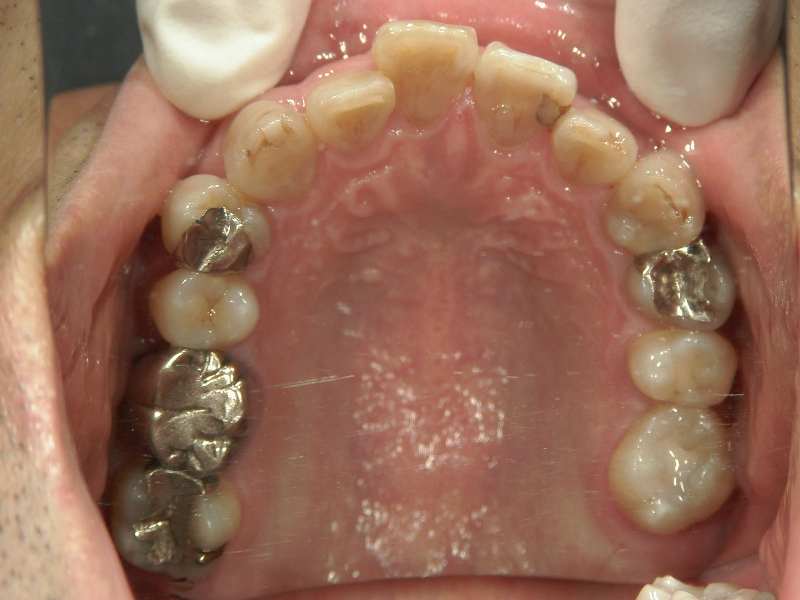

矯正歯科 治療前矯正歯科 治療前

矯正歯科 治療前 右上4番、左右下4番 計3本抜歯し、叢生を改善

矯正_灰色.pngno.22_8175_治療前_上.jpg矯正_灰色.png